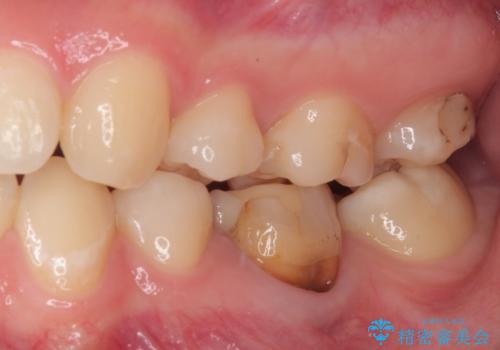

- 神経を取り除いた後に歯の色が変色して気になってきたとのことで来院された患者様です。

前歯は片側のみ神経を取り除かれていましたが、反対側もむし歯治療の詰め物が広範囲に及んでいたため、両方の歯をオールセラミッククラウンにて補綴治療を行うこととしました。

奥歯も著しく茶色に変色していたため、同様にオールセラミッククラウンにて補綴治療を行うこととしました。